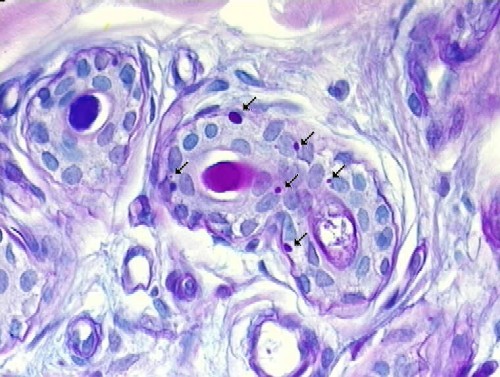

Lafora bodies in the cortex of a dog with myoclonic epilepsy:

Immunohistochemistry and Ultrastructural Findings

- Lafora body reacts with antibodies against ubiquitin

- KM-279 antibody also reacts with Lafora bodies, corpora amylacea, basophilic masses in the heart, filamentous glycogen inclusions in type IV glycogenosis, and Bielschowsky bodies

- 160kD and 200kD neurofilament, and desmin antibodies also react with Lafora bodies

- still unclear if mutant Laforin is in the Lafora bodies

- polyglucosan bodies - in axons

- Lafora bodies - in neuronal perikarya and dendrites

Lafora bodies (temporal lobectomy)